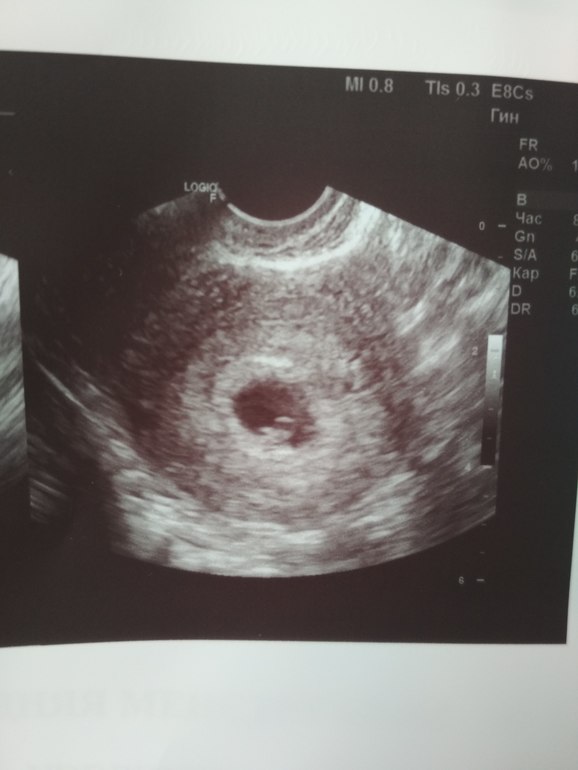

Я тоже уже записывалась на УЗИ и как раз будет так же 6 недель 6 дней..теперь дождаться бы 9 июля 🤪 и тоже в Медэксперт иду)